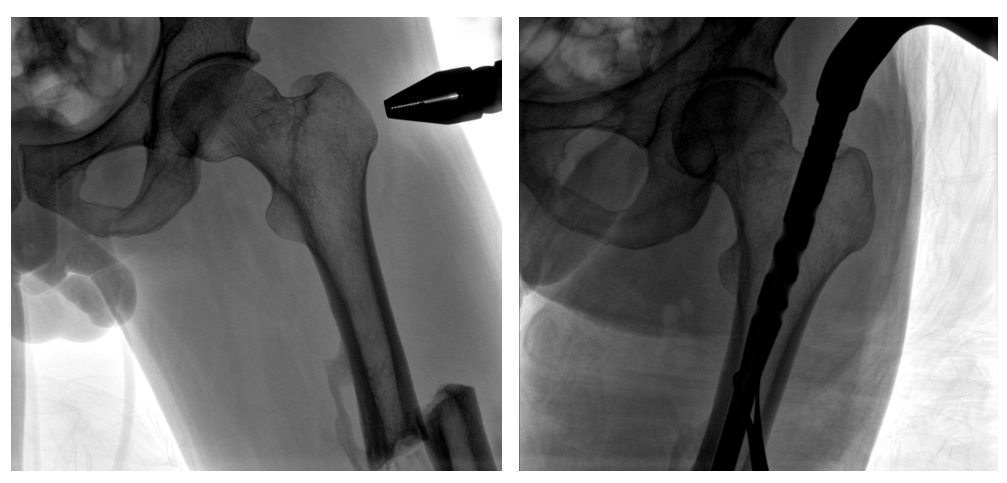

移動(dòng)式一體化C形臂釘點(diǎn)至骨折部位的臨床影像

普愛(ài)醫(yī)療PLX119C大平板一體式C形臂采用30CM×30CM的平板探測(cè)器,在脊柱和長(zhǎng)骨骨折等骨科手術(shù)治療中,獲取更大視野、更清晰的骨折部位圖像,能夠有助于醫(yī)生在術(shù)中及時(shí)了解和評(píng)估骨折部位的對(duì)位、對(duì)線情況,且能進(jìn)行長(zhǎng)度和角度測(cè)量,為進(jìn)一步提高手術(shù)質(zhì)量提供強(qiáng)有力的支持。